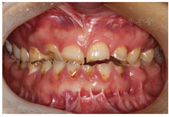

(1)面部检查:面部外形不对称,颏部居中,两侧口角高度不一致,面下1/3高度减小,两侧颧弓突度一致,下颌前突。中位笑线,上唇长度适中(图1)。(2)关节检查:颞颌关节:弹响(-),杂音(-),疼痛(-)。开口度正常,开口型有偏斜,肌肉触诊压痛:右侧上颌结节(+)、左侧上颌结节(++)、双侧翼内肌(+),其他肌肉及颞下颌关节区未诉异常,关节载荷实验无任何紧张和疼痛不适。(3)口内检查:上下颌牙中线较面中线向右偏斜,前后牙广泛不均匀磨耗,前牙磨耗后呈刃状;14、21、22、23及下颌牙唇颊侧颈部见釉质缺损,部分牙本质暴露,呈黄褐色,少量白垩色;44牙见开髓孔,表面暂封。12缺失,缺失牙间隙无。全口牙龈色形质未见异常,11牙、21牙唇侧牙龈龈缘高度不一致,21牙较11牙龈缘高约3mm。全口口腔卫生状况良好,菌斑、软垢少量,未及牙石及牙周袋。咬合检查:11-14牙与对颌牙反

,21牙与31、31牙对刃,左侧尖牙至前磨牙深覆盖,

曲线不平(图2,图3)。(4)影像学检查: